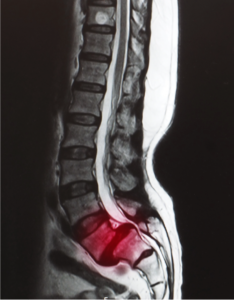

Lumbar Disc Herniation

Lumbar disc herniation is the most common cause of low back pain and leg pain (sciatica). The lumbar intervertebral discs are flat and round.